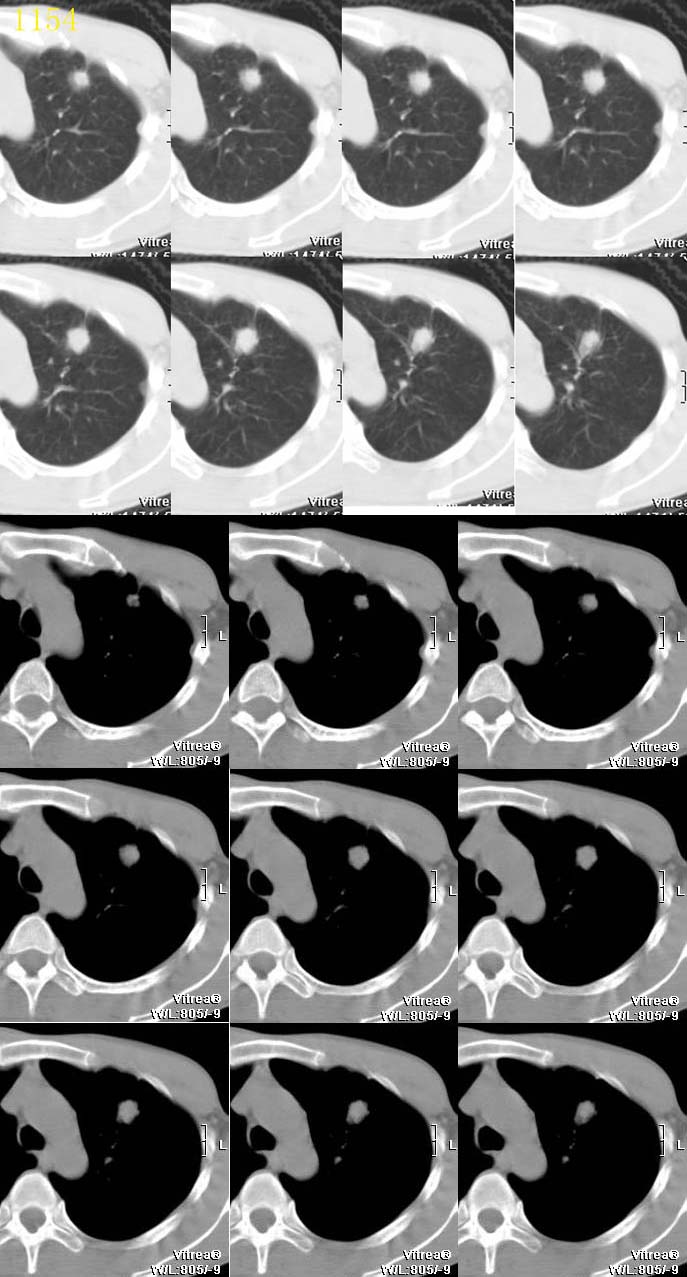

ct1154 听蝉观竹提供 结果-------肺小细胞癌

http://www.radida.com/radinet/read.php?tid=3361